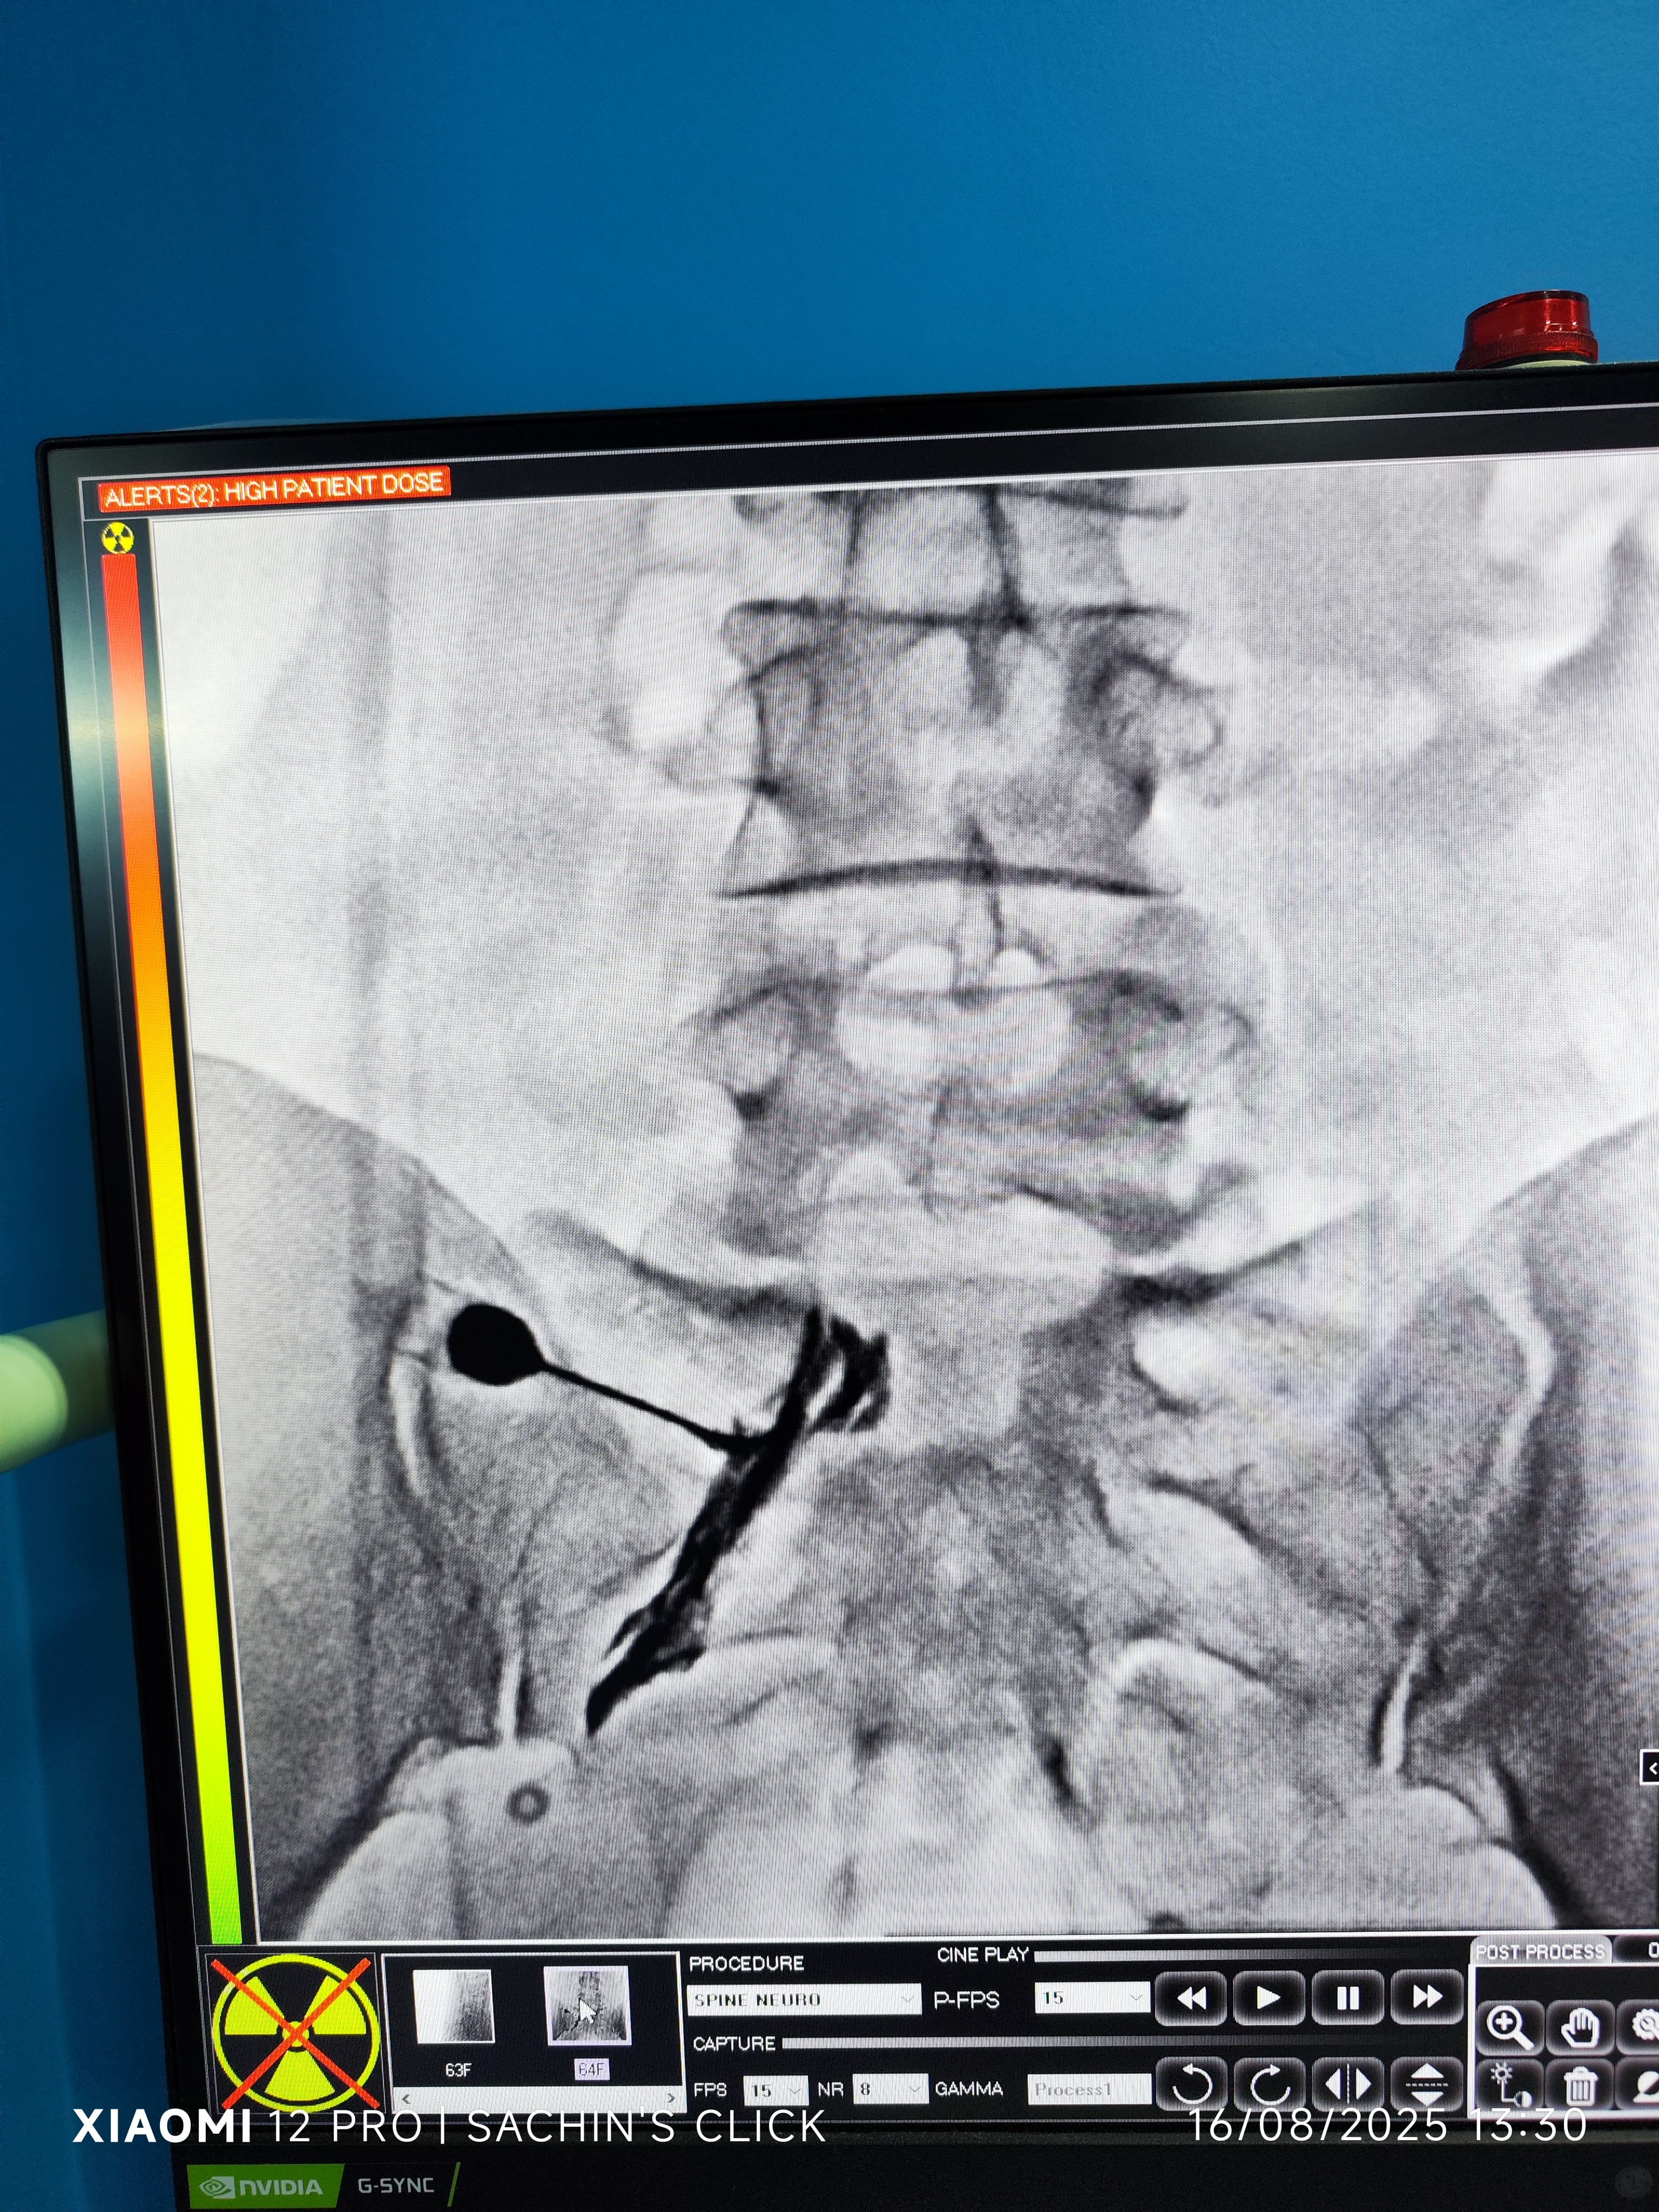

Glimpses of Advance Pain Care

Step inside our clinic and see our commitment to a healing environment and advanced care.